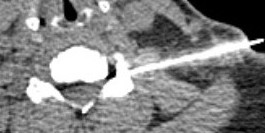

CT

May add complementary information to MRI

- posterolateral impingement from uncovertebral spur

- ossification of the PLL

- transforaminal injections with CT

- interlaminar injections with CT